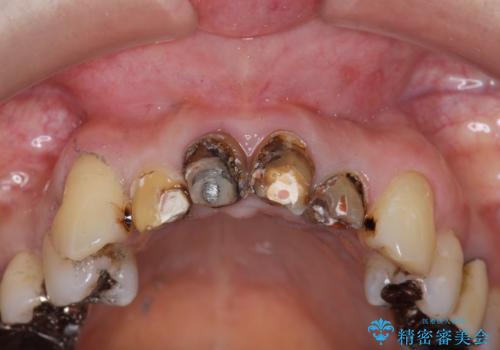

前歯の黒ずみ セラミッククラウン改善

- 20年前に治療した前歯の劣化・審美障害の改善を求めて来院されました。

クラウンを除去し審美的なジルコニアクラウンによる補綴の再作製計画を立案します。

クラウンと支台の適合が悪いと内部に汚れがたまり虫歯の再発・審美性の障害・口臭の発生リスク方あまります。